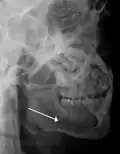

lateral oblique image demonstrating a fractured mandible.